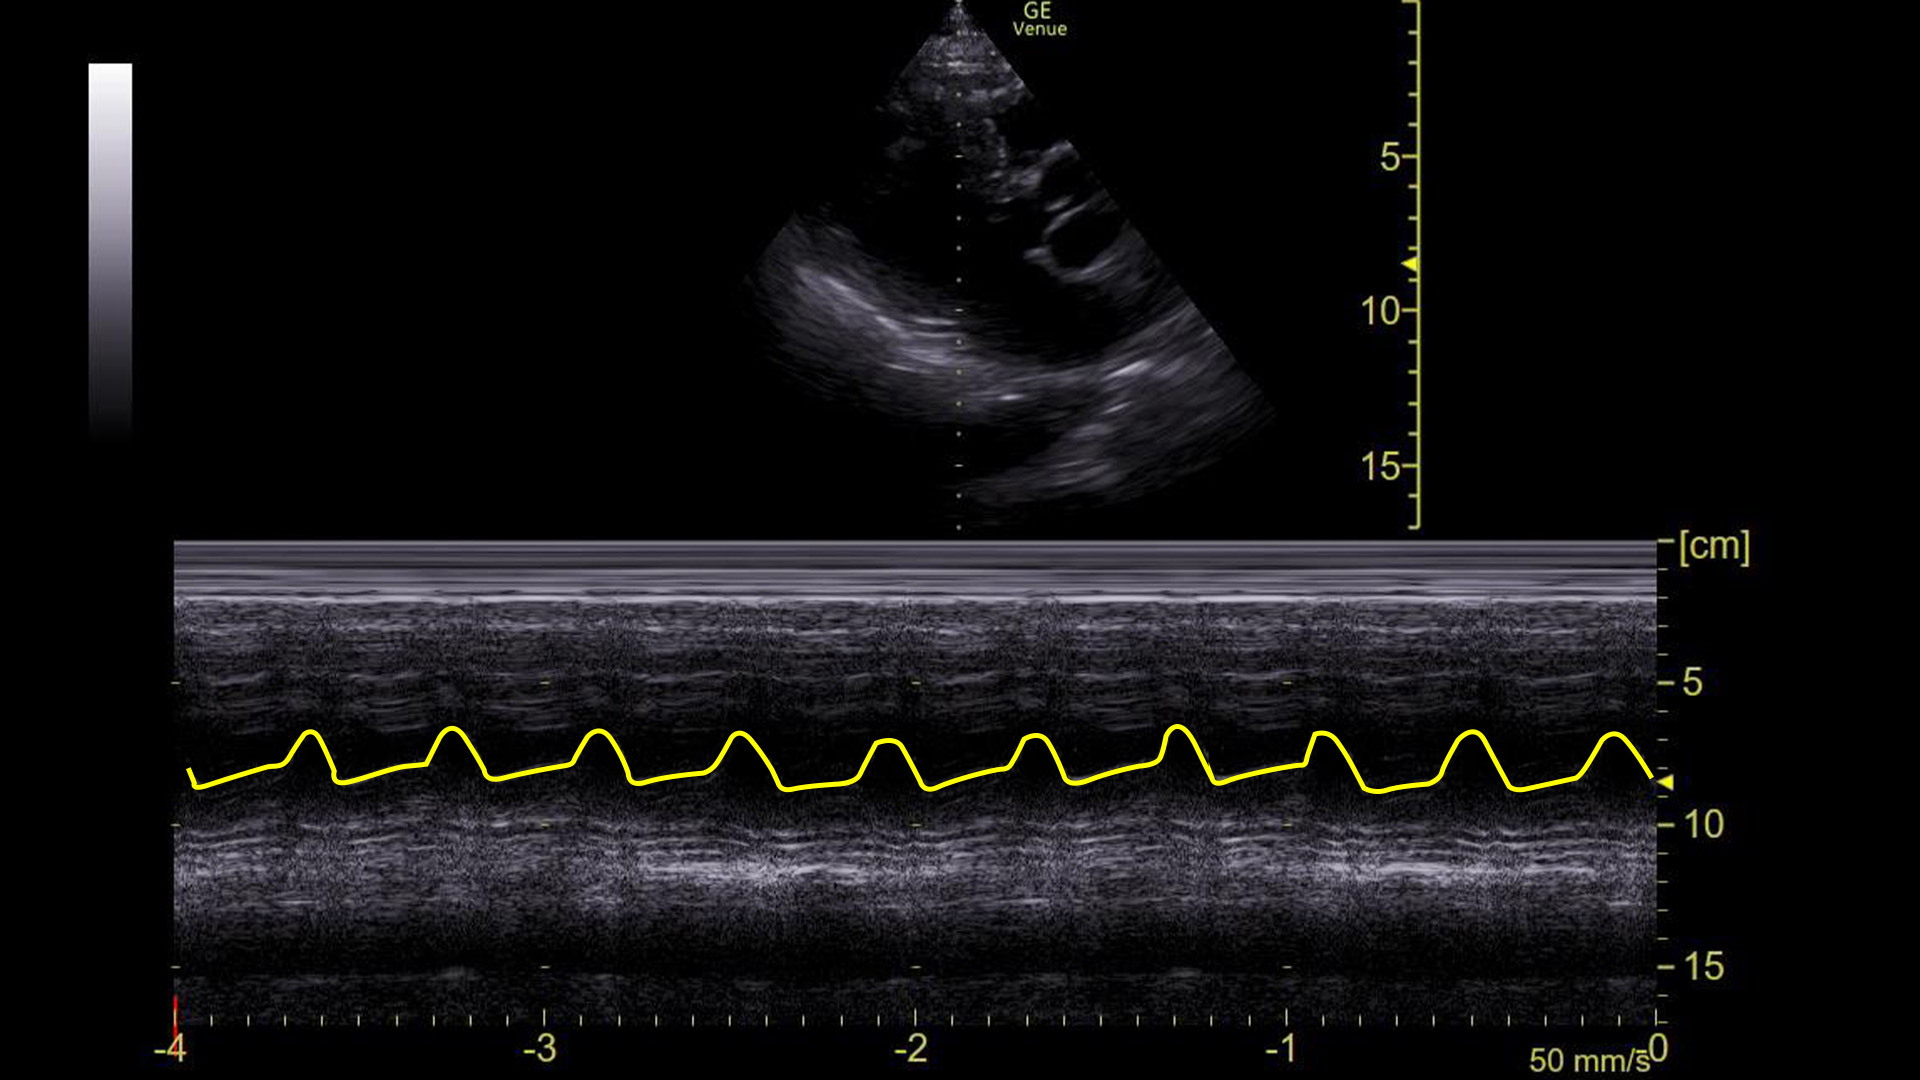

Here it is with the area of interest highlighted.

What we are looking at here is the movement of the mitral valve within the left ventricle – specifically what is highlighted in yellow is the movement of the anterior leaflet of the mitral valve. (Recall that it has two leaflets: anterior and posterior.)

You can see that the leaflet flaps once per cardiac contraction. That, however, is ABNORMAL!

The point is, that in a sinus rhythm, the mitral valve opens not once, but twice for every contraction: Once during ventricular relaxation (passive ventricular filling) and a second time during atrial contraction.

We can see this on ultrasound as demonstrated above. Graphically on the screen, the first movement is called the E-wave, and the second is called the A-wave.

Compare that to the tracing before the cardioversion:

There are no A-waves.

This tells us that the atria are not contracting in an organized, functional way because the mitral valve is only flapping once during each heart beat.

This cannot be a sinus rhythm. However, it does not necessarily identify what the arrhythmia is. Atrial fibrillation would certainly look like this, although it would probably not be this regular. Atrial flutter with 2:1 block would look like this**. “SVT” would look this way as well as would ventricular tachycardia. The point is that the absence of A-waves at the mitral valve rules out normal atrial contractions, but does not, by itself, define a particular arrhythmia.